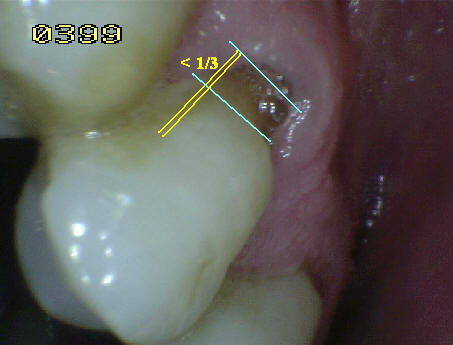

- Cuando una lesión cariosa en

una superficie de la raíz, se extiende más allá del

ángulo de la línea de la raíz pero implica al menos

1/3 de la distancia a través de la superficie

adyacente, esa superficie adyacente también se debe

calificar como caries. Si es menor (< 1/3) se

codificará como sana. Ver imagen derecha.